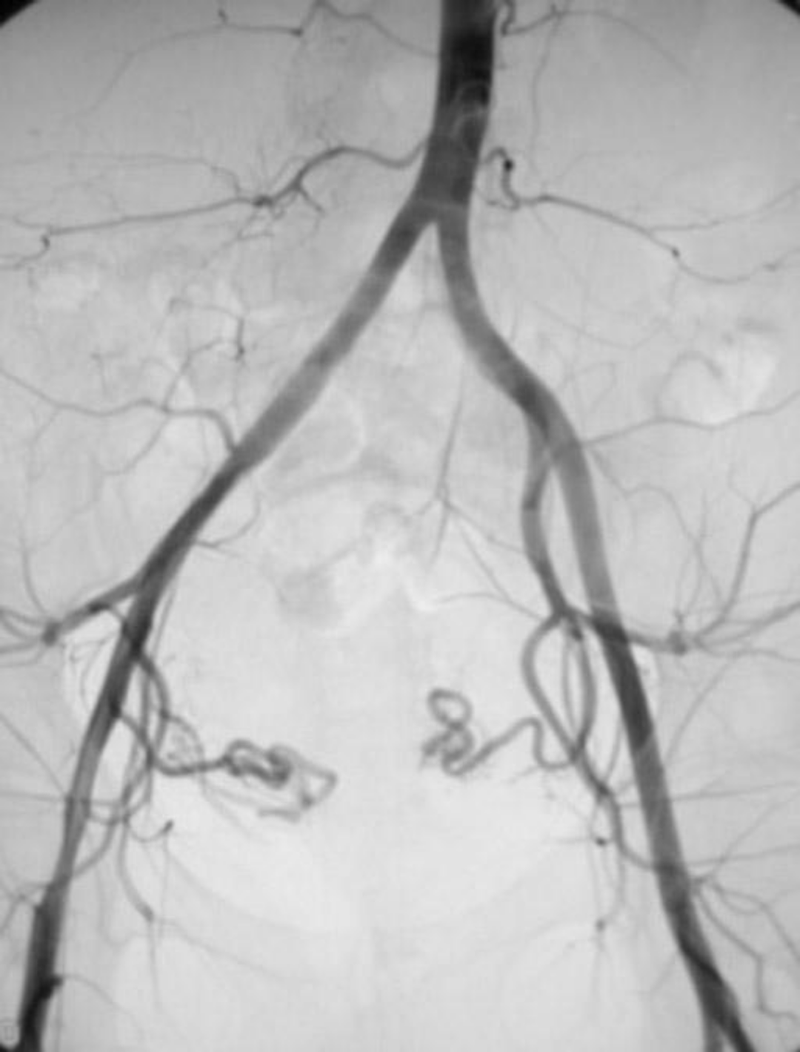

pre UFE (Uterine fibroid embolization) angiogram

Obgyn

Uterine

Fibroid